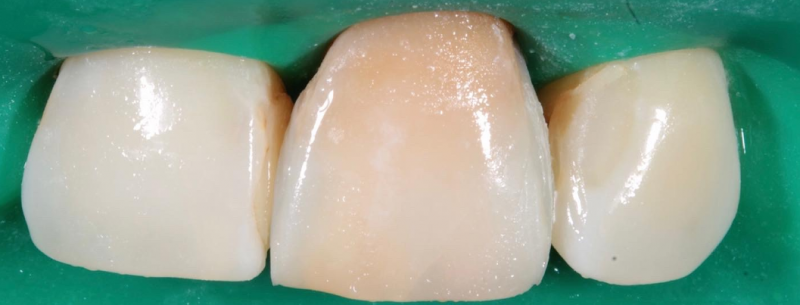

На странице представлено портфолио стоматологий Санкт-Петербурга с работами до и после профессиональной чистки зубов. В нашем портфолио собраны разные клинические случаи: от удаления незначительного налета до снятия массивного поддесневого камня. Здесь вы можете увидеть, как возвращается естественный цвет и внешний вид зубов после процедуры. Изучите результаты до и после чистки зубов, чтобы увидеть реальный эффект и выбрать клинику в Санкт-Петербурге, где профессиональная гигиена поможет вернуть зубам здоровый вид.

Чистка зубов Air-flow